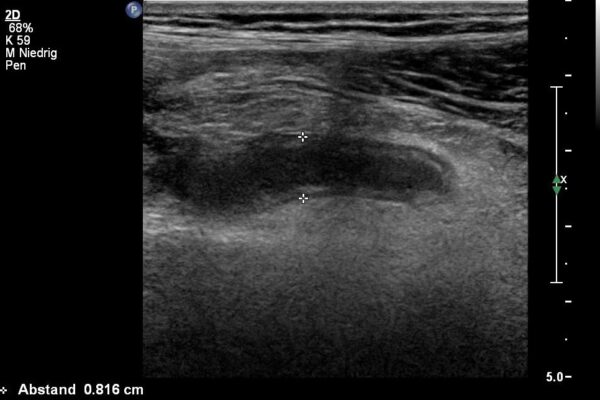

Mit hochauflösenden 18MHz Sonden lassen sich Gelenke, Muskeln, Sehnen und Bänder gut untersuchen.

Die small parts sind eine sehr inhomogene Gruppe von Organen oder Weiteilveränderungen. In dieser Gruppe finden sich oft Untersuchungen der Schilddrüse, der Lymphdrüsen, der weiblichen Brust, der Hoden oder der Haut/Unterhaut.

- Haut/Unterhaut: entzündliche Schwellungen, Knötchen (Lipome).